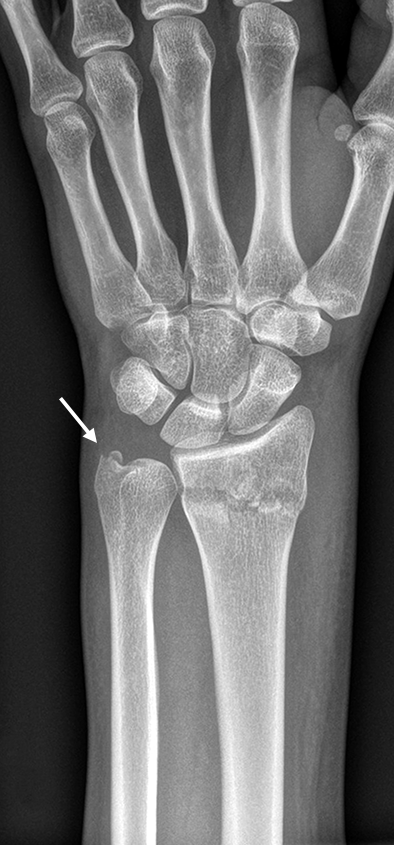

The patient was a 25-year-old woman who sustained a displaced, unstable extraarticular fracture of the left distal radius while snowboarding.

After closed reduction a dorsal re-dislocation of 25° occurred (Fig 4a). There are additional apparent signs of instability: dorsal comminution (Fig 4a) and fracture of the ulnar styloid (Fig 4b). Therefore, a considerable potential for further dislocation is present which is likely to occur in a cast. This young, active, and demanding patient wishes to return to her activities as early as possible. This can only be achieved with an operative fracture fixation. The nail was chosen instead of a plate. This allowed an almost instant functional use of her hand, which allowed her to return to work at 2 weeks postoperatively without additional fixation or a splint and full unprotected function of her wrist at 6 weeks.